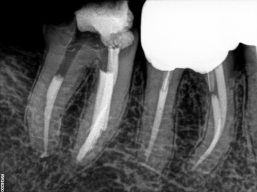

O instrumento Ultrassônico específico escolhido deve ter um comprimento que alcance a obstrução e um diâmetro pequeno o bastante para fornecer visão direta no instrumento fraturado. Esta ponta de inserção é colocada contra a cabeça do seguimento fraturado no interior do canal, ativada e movida na direção anti-horária em torno da obstrução. Esse trabalho ultra-sônico utiliza o Stropko Irrigador (stropko.com) com uma cânula luer-lock de 29 ga(Ultradent Producs) para fornecer uma corrente contolada de ar, que serve para soprar a apoeira dentinária e manter a visão contínua.

O objetivo deste método ultra-sônico é trefinar, lixar a dentina e expor 2 a 3 mm do aspecto mais coronário da obstrução, ou cerca de um terço de seu comprimento total. Algumas gotas de uma solução de 17% de EDTA são pingadas no canal e servem como um adjuvante de remoção potente ao colocar uma ponta energizada contra a cabeça de um segmento de lima quebrado. Clinicamente, depois de criar uma plataforma de preparo e expor a cabeça de um segmento de lima quebrado, colocar gentilmente a ponta energizada entre a lima afunilada e a parede do canal afunilado muitas vezes faz com que o instrumento quebrado se solte, desenrosque e saia do canal. No entanto, procedimentos ultra-sônicos podem não ser bem-sucedidos e, nesses casos, um método de remoção secundária será necessário.

Veja também esse caso complexo de remoção de pino em um canal calcificado.